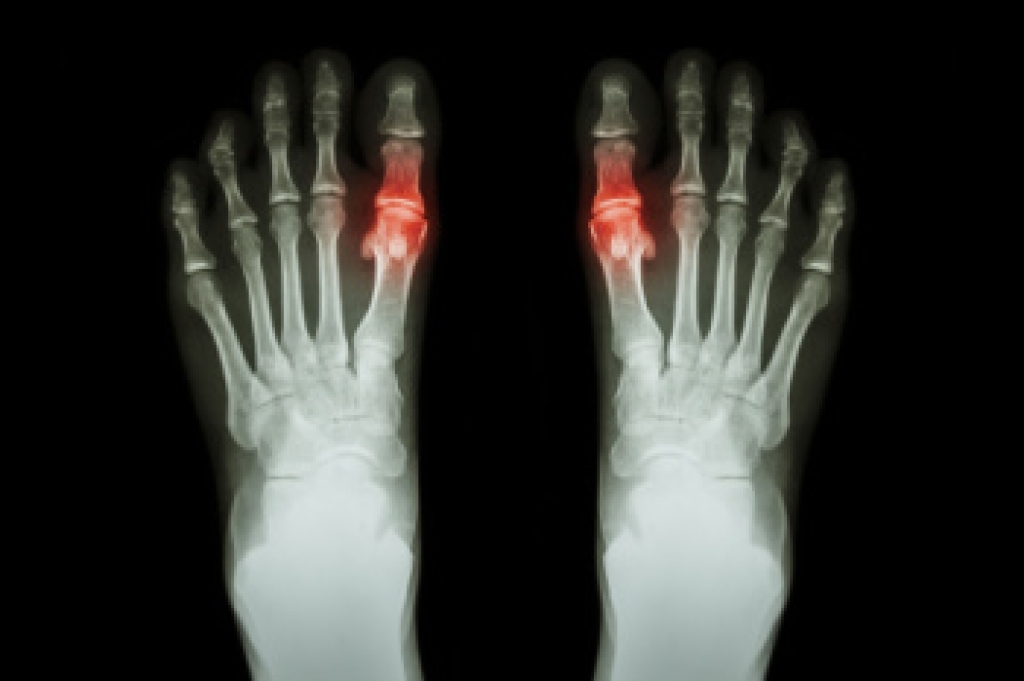

Foot and ankle injuries are a common occurrence when it comes to athletes of any sport. While many athletes dismiss the initial aches and pains, the truth is that ignoring potential foot and ankle injuries can lead to serious problems. As athletes continue to place pressure and strain the area further, a mild injury can turn into something as serious as a rupture and may lead to a permanent disability. There are many factors that contribute to sports related foot and ankle injuries, which include failure to warm up properly, not providing support or wearing bad footwear. Common injuries and conditions athletes face, including:

- Plantar Fasciitis

- Achilles Tendinitis

- Achilles Tendon Rupture

- Ankle Sprains